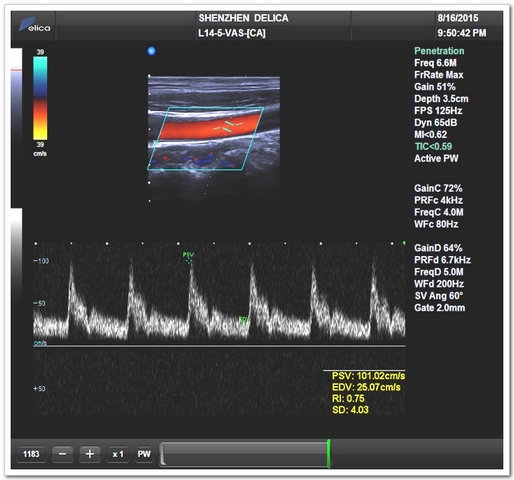

彩超模式(颈总动脉)

彩超模式(椎动脉)